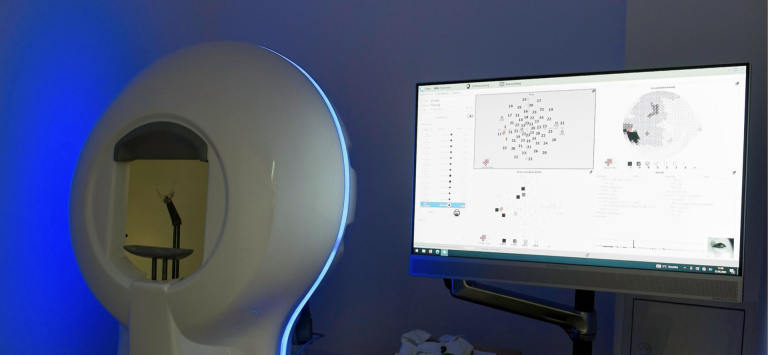

Gesichtsfeld

In der modernen Augenheilkunde spielt das Gesichtsfeld eine entscheidende Rolle bei der Diagnostik und Überwachung von Augenerkrankungen. Der Augenarzt nutzt dabei die innovativsten Technologien, um präzise und umfassende Untersuchungen durchzuführen. Mit High-Tech-Geräten wie dem Perimetriegerät können detaillierte Gesichtsfeldanalysen erstellt werden, die selbst kleinste Veränderungen im Sehvermögen frühzeitig erkennen. Dieser fortschrittliche Ansatz ermöglicht nicht nur eine exakte Diagnostik, sondern auch eine personalisierte Therapieplanung, um die Gesundheit der Augen nachhaltig zu fördern.